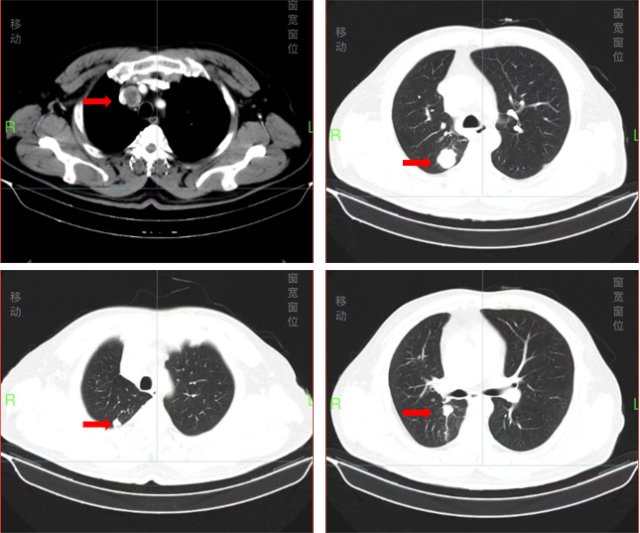

进入我科 CT 检查(2024.7.10)

PET-CT 检查(2024.7.11)